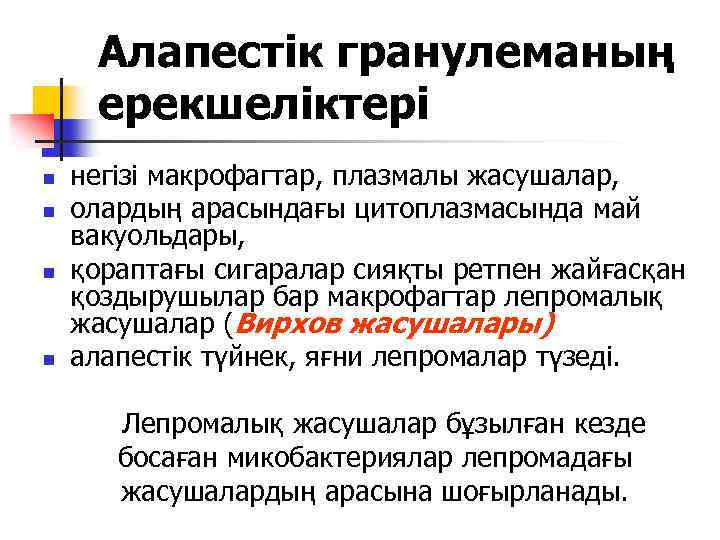

Алапестік гранулеманың ерекшеліктері n n негізі макрофагтар, плазмалы жасушалар, олардың арасындағы цитоплазмасында май вакуольдары, қораптағы сигаралар сияқты ретпен жайғасқан қоздырушылар бар макрофагтар лепромалық жасушалар (Вирхов жасушалары) алапестік түйнек, яғни лепромалар түзеді. Лепромалық жасушалар бұзылған кезде босаған микобактериялар лепромадағы жасушалардың арасына шоғырланады.